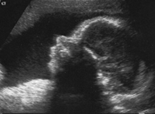

Prenatal Diagnostics / Ultrasound

Pränataldiagnostik/ Ultraschall

• Malformation diagnostics

• Doppler sonography

• 3-D-Sonography